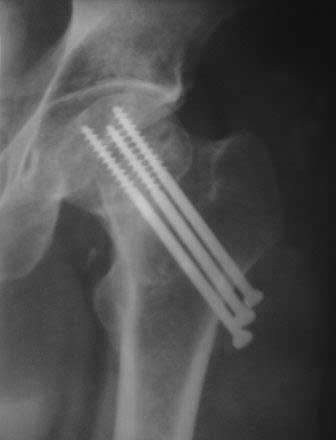

[Ortho] Ложный сустав шейки бедра

последний  Р-снимок